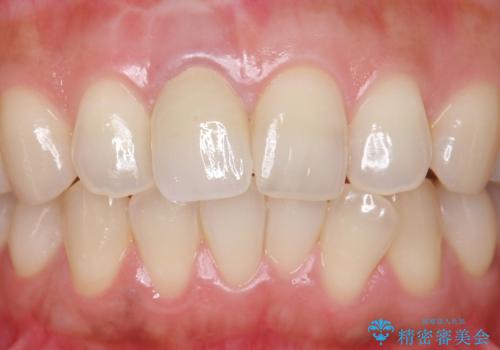

- もっと自然にみえるような差し歯にしたいと希望され来院された患者様です。

患者様の天然歯はグラデーションがあり切縁(歯冠の先端)はやや透けていて透明感があるのに対し、前歯(右上1)の差し歯はやや黄色く不透明で単調な色味でした。

患者様のご希望により、右上1はジルコニアクラウン(スペシャル)、右上5はジルコニアクラウン(スタンダード)へやりかえることにしました。

前歯のクラウンは一度修正し、患者様の理想とする色味や形態を追求しました。

天然歯と見紛うほどの自然な仕上がりに喜んで頂けました。

ジルコニアクラウンの繊細なグラデーション・透明感は熟練した技工士さんの技術の賜物です。

右上1:ジルコニアクラウン スペシャル

右上5:ジルコニアクラウン スタンダード